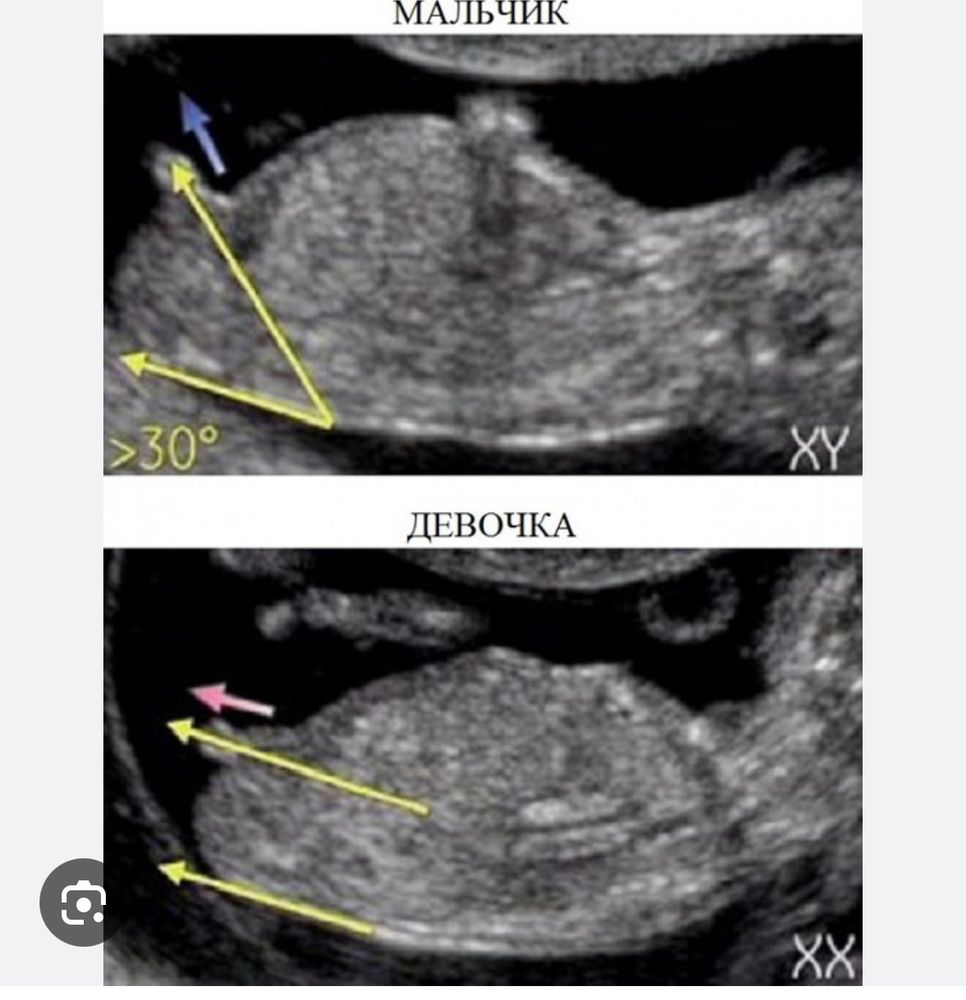

1 скрининг ,кто -нибудь разбирается в поле ребёнка ?)

По мне на девочку похоже очень.

Анна, почему-то я уверенна, что если мальчик, то на первом скринге узистка говорит 100% А если девочка, то на первом почему-то легко спутать с мальчиком

Зай, да мне сына на 1-ом сразу сказали и не ошиблись)

Qazplm, у вас больше вроде на девчулю